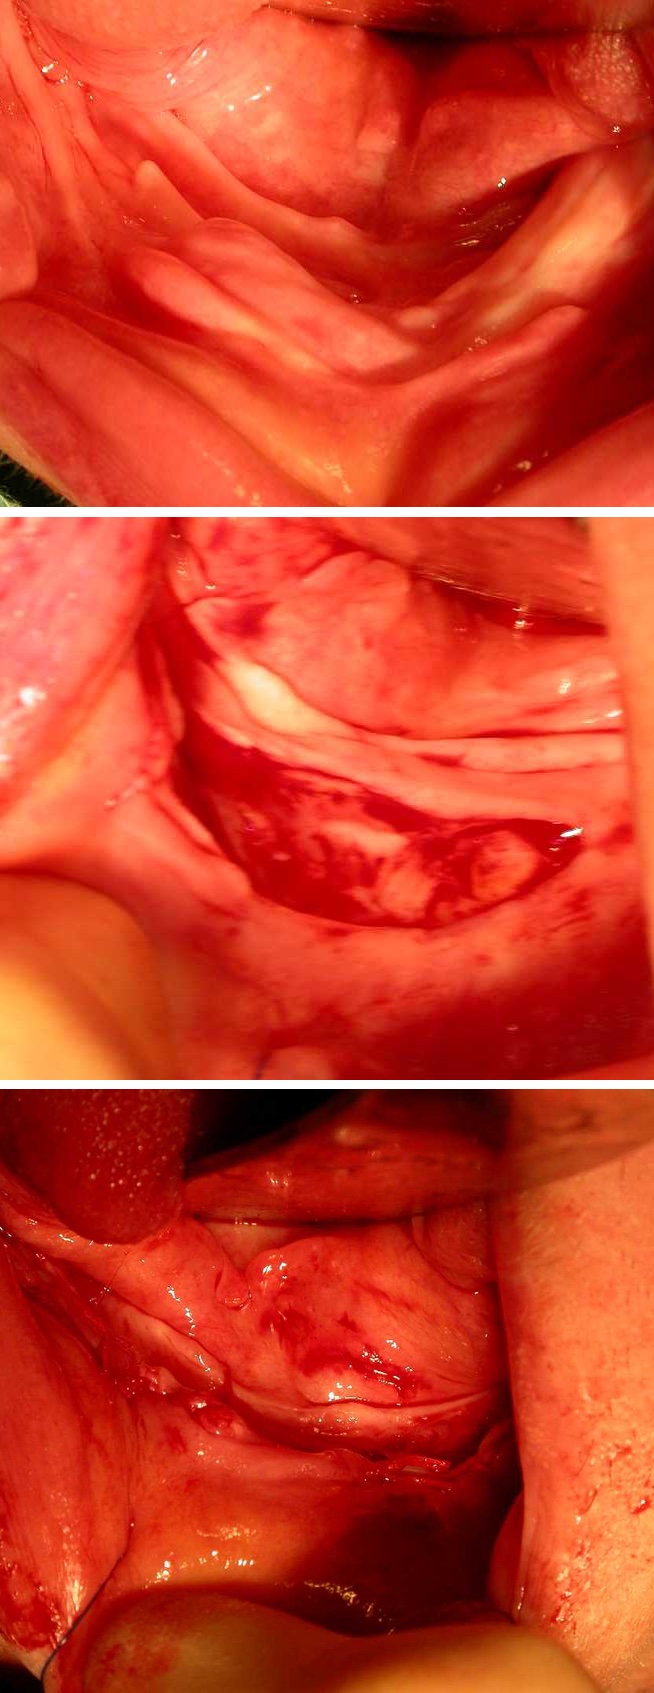

Where the residual hyperplastic tissue will interfere with denture construction, excision is indicated (Figure 2). This may take the form of a simple excision, with elliptical excision of the excess tissue at its base. In large areas of hyperplasia, simple excision may create a shallow V-shaped sulcus. In these cases, a mucosal-preserving approach should be attempted, by dissecting and preserving the buccal / labial mucosa while excising the remainder of the hyperplastic lesion. The preserved mucosa is inlaid as a graft to preserve sulcus depth. In this case, a healing baseplate suitably lined with tissue conditioner is essential to try to maintain sulcus depth.

Figure 2: Top: irritation hyperplasia; middle: excision of irritation hyperplasia; bottom: mucosa should be preserved wherever possible.